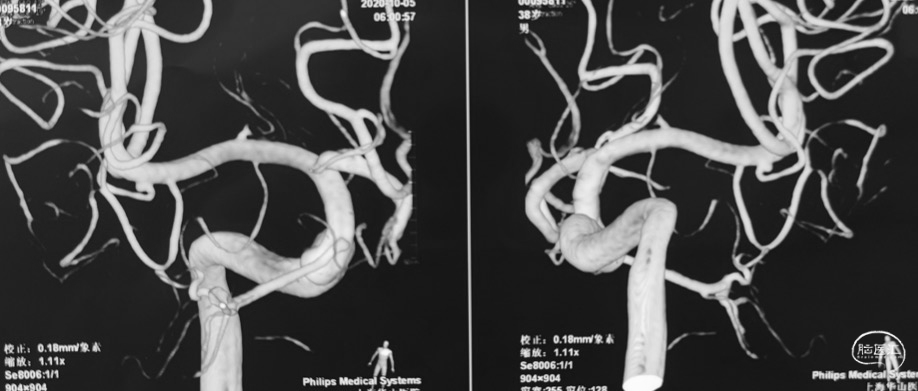

术前DSA

右侧

左侧

男性,38岁。

主诉:突发头痛、头晕1天。

1. 蛛网膜下腔出血

2. 左侧大脑中动脉分叉部动脉瘤